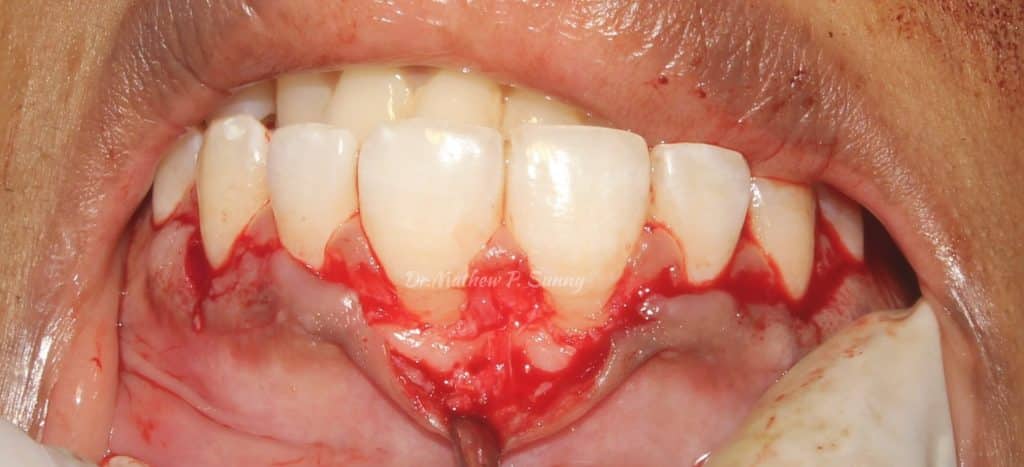

osseous recontouring done to establish 3 mm biological width..

for left canine..